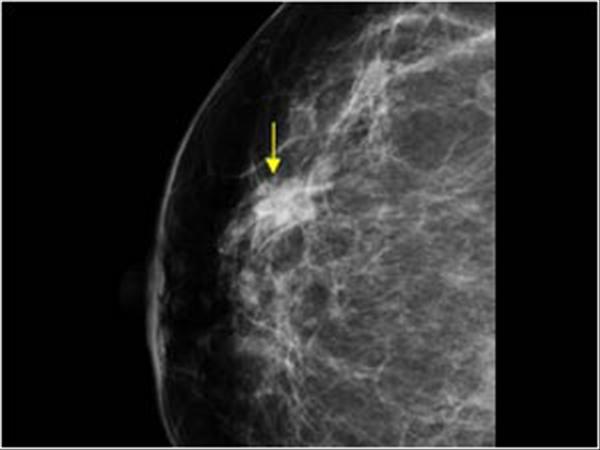

Ung thư vú

» Thông tin: Nữ giới – 59 tuổi.

» Lâm sàng: Khối tuyến vú.